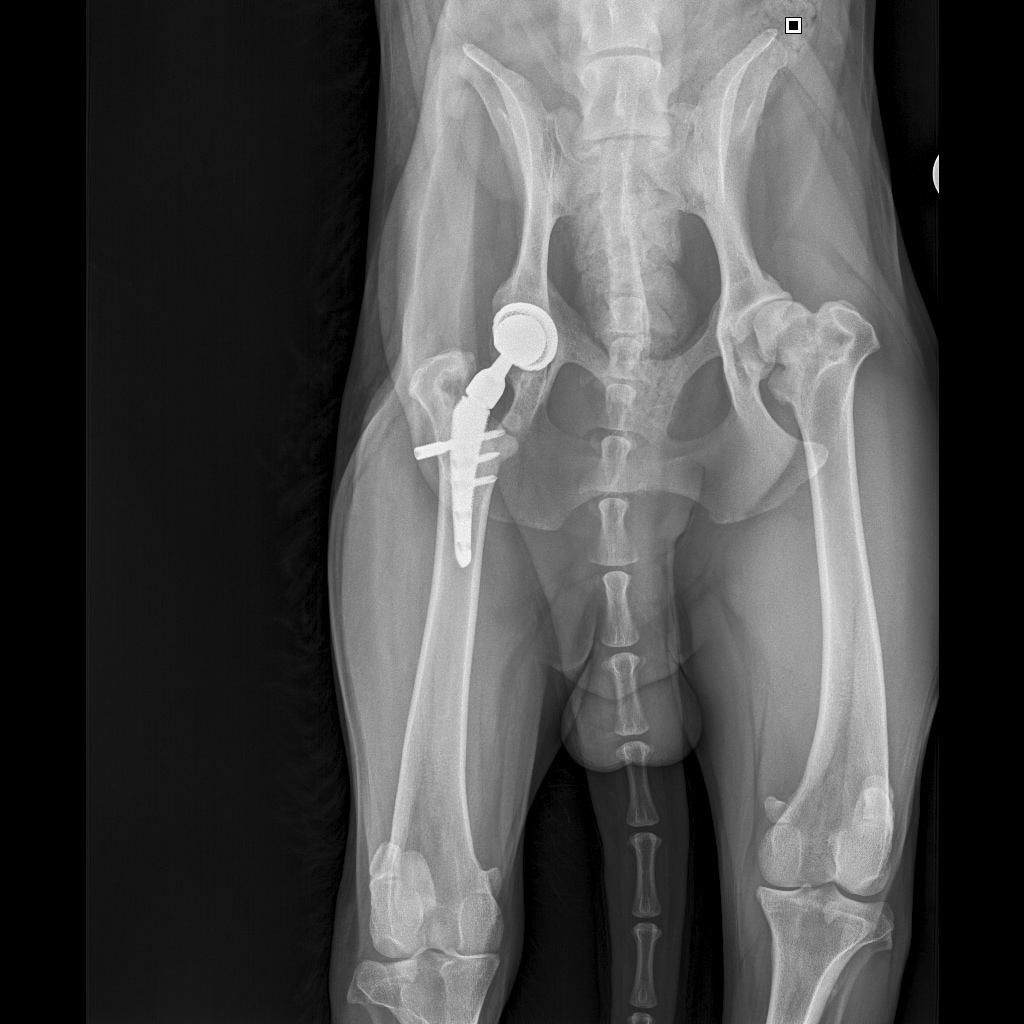

26 августа к 10 утра голодными, нас ждут на контрольный рентген в клинике на Вернадского.

Рентген будет под седацией

За время противовоспалительной терапии снизилось воспаление и в левом тазобедренном суставе, но увы, форма головки бедренной кости и состояние шейки бедра , лучше не стали:(((

Операция однозначно нужна.

Снимки столь качественные, что их можно в учебник